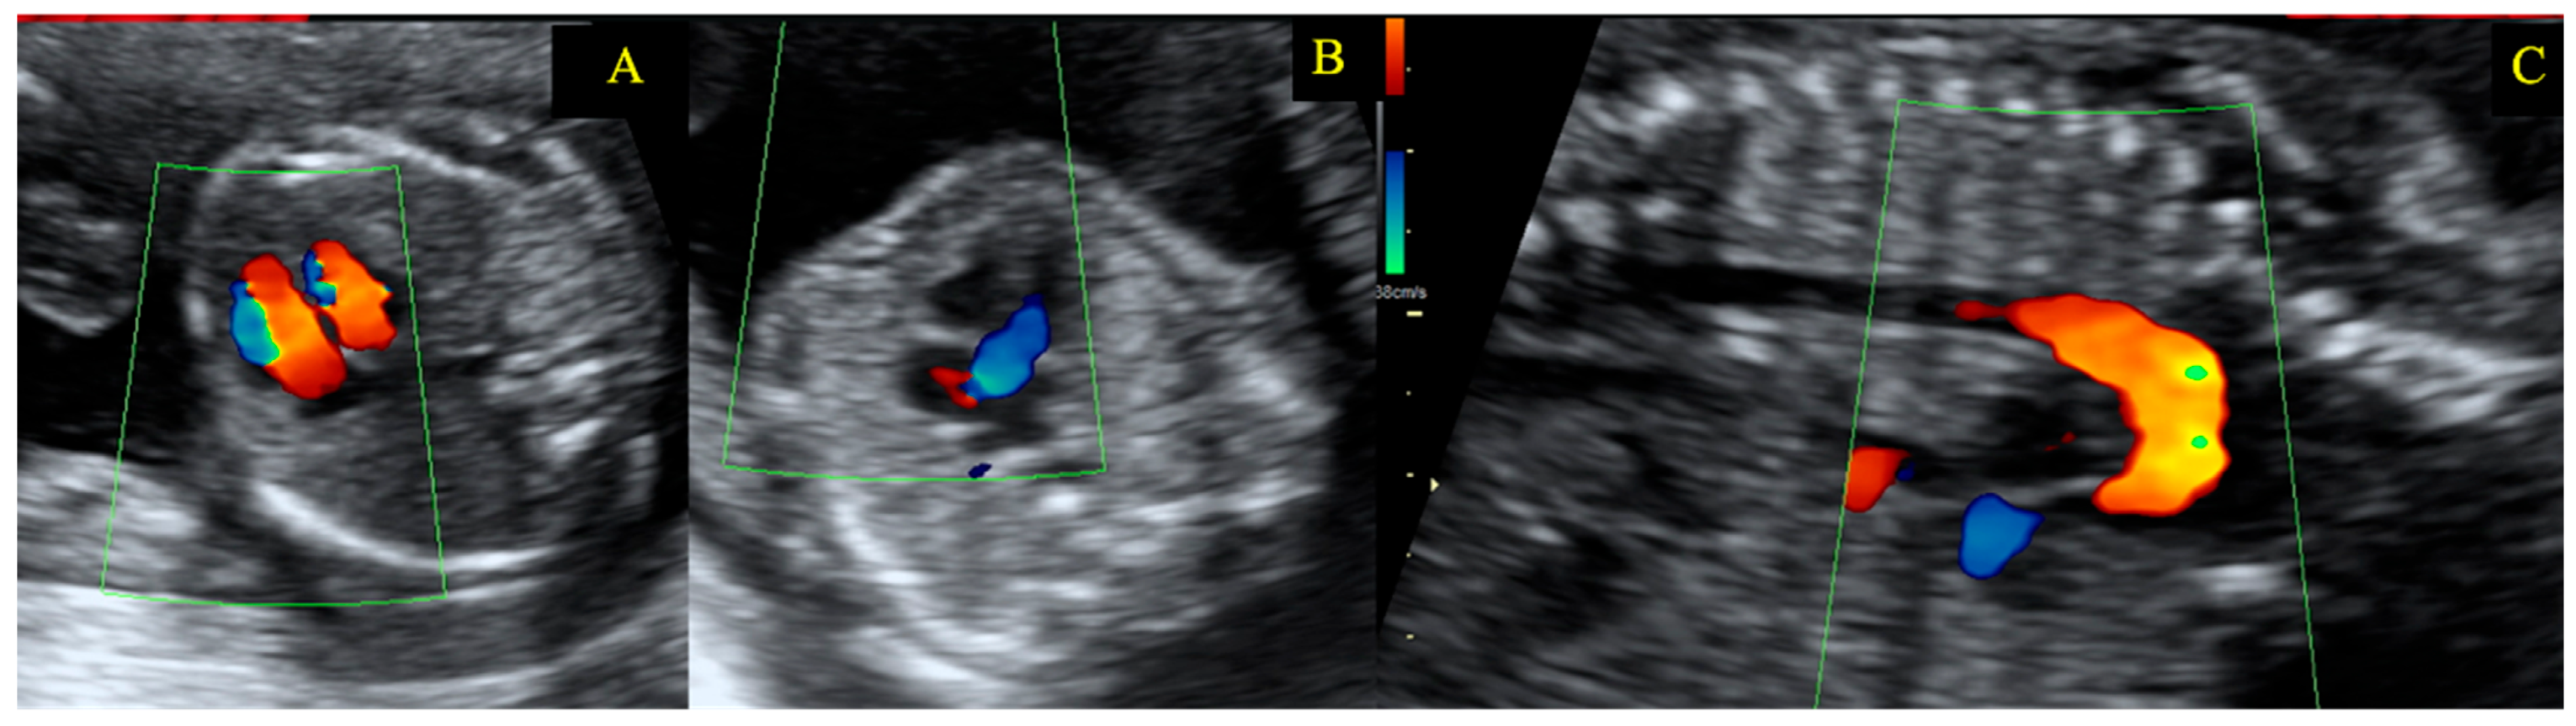

| Gestational Age (Weeks) | Heart Rate (bpm) | Hb (g/dL) | NT-proBNP (pg/mL) | 6mWT (m) | LVEF (%) | LVOT VTI (cm) | AV VTI (cm) | Maximum AV Gradient (mmHg) | Mean AV Gradient (mmHg) | Indexed Aortic Valve Area (cm2/m2) |

|---|---|---|---|---|---|---|---|---|---|---|

| 22 | 76 | 11.5 | 45 | 670 | 59 | 27.5 | 99.3 | 96 | 58 | 0.475 |

| 26 | 73 | 60 | 27.3 | 99.2 | 94 | 60 | 0.475 | |||

| 29 | 82 | 11.4 | 59 | 625 | 60 | 26.9 | 99.8 | 93 | 60 | 0.463 |

| 30 | 85 | 61 | 27 | 102 | 108 | 60 | 0.457 | |||

| 31 | 81 | 60 | 26.9 | 101.8 | 95 | 58 | 0.469 | |||

| 32 | 78 | 12.1 | 67 | 630 | 59 | 27.2 | 100 | 103 | 62 | 0.469 |

| 33 | 76 | 59 | 27.5 | 99.5 | 100 | 61 | 0.475 | |||

| 34 | 84 | 61 | 27.9 | 101 | 101 | 60 | 0.475 | |||

| 35 | 82 | 12.5 | 37 | 615 | 61 | 28 | 100.6 | 95 | 55 | 0.481 |

| 36 | 80 | 60 | 26.4 | 99 | 89 | 52 | 0.463 | |||

| 37 | 85 | 12.6 | 62 | 27 | 100 | 93 | 56 | 0.469 | ||

| 38 | 86 | 12.3 | 66 | 575 | 62 | 26.5 | 99.8 | 92 | 55 | 0.457 |

| 3 months postpartum | 70 | 11.9 | 54 | 654 | 60 | 28.3 | 118 | 103 | 68 | 0.50 |